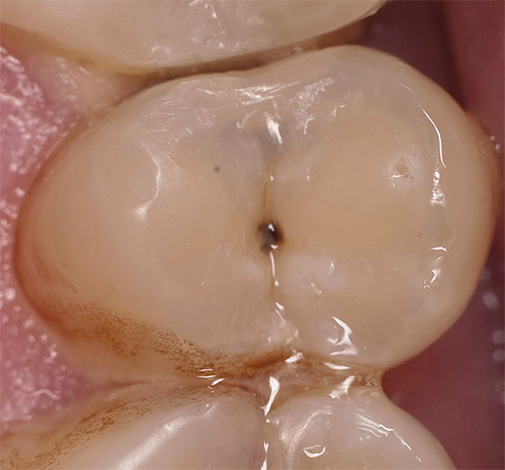

Nella foto sotto - la carie interna sui tessuti sotto lo smalto distrutto. Questo è un tipo tipico di malattia che si sviluppa all'interno del dente. Le aree scure della dentina interessata sono chiaramente visibili:

È il cambiamento di colore dei tessuti danneggiati dalla carie che è il principale segno diagnostico della malattia. Nella stragrande maggioranza dei casi, è proprio sui punti neri sullo smalto o sulle fessure che il medico fa in modo inequivocabile la diagnosi di carie.